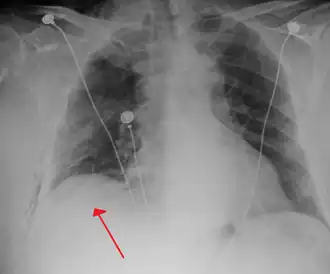

Chest X-ray

A plain chest radiograph, ideally with the X-ray beams being projected from the back (posteroanterior, or "PA"), and during maximal inspiration (holding one's breath), is the most appropriate first investigation.[35] It is not believed that routinely taking images during expiration would confer any benefit.[36] Still, they may be useful in the detection of a pneumothorax when clinical suspicion is high but yet an inspiratory radiograph appears normal.[37] Also, if the PA X-ray does not show a pneumothorax but there is a strong suspicion of one, lateral X-rays (with beams projecting from the side) may be performed, but this is not routine practice.[18][22]

-

Anteroposterior inspired X-ray, showing subtle left-sided pneumothorax caused by port insertion -

Lateral inspired X-ray at the same time, more clearly showing the pneumothorax posteriorly in this case -

Anteroposterior expired X-ray at the same time, more clearly showing the pneumothorax in this case -

Chest X-ray showing a pneumothorax on the right (left in the image), where the absence of lung markings indicates that there is free air inside the chest -

Chest X-ray showing the features of pneumothorax on the left side of the person (right in image)

It is not unusual for the mediastinum (the structure between the lungs that contains the heart, great blood vessels, and large airways) to be shifted away from the affected lung due to the pressure differences. This is not equivalent to a tension pneumothorax, which is determined mainly by the constellation of symptoms, hypoxia, and shock.[16]

The size of the pneumothorax (i.e. the volume of air in the pleural space) can be determined with a reasonable degree of accuracy by measuring the distance between the chest wall and the lung. This is relevant to treatment, as smaller pneumothoraces may be managed differently. An air rim of 2 cm means that the pneumothorax occupies about 50% of the hemithorax.[18] British professional guidelines have traditionally stated that the measurement should be performed at the level of the hilum (where blood vessels and airways enter the lung) with 2 cm as the cutoff,[18] while American guidelines state that the measurement should be done at the apex (top) of the lung with 3 cm differentiating between a "small" and a "large" pneumothorax.[38] The latter method may overestimate the size of a pneumothorax if it is located mainly at the apex, which is a common occurrence.[18] The various methods correlate poorly but are the best easily available ways of estimating pneumothorax size.[18][22] CT scanning (see below) can provide a more accurate determination of the size of the pneumothorax, but its routine use in this setting is not recommended.[38]

Not all pneumothoraces are uniform; some only form a pocket of air in a particular place in the chest.[18] Small amounts of fluid may be noted on the chest X-ray (hydropneumothorax); this may be blood (hemopneumothorax).[16] In some cases, the only significant abnormality may be the "deep sulcus sign", in which the normally small space between the chest wall and the diaphragm appears enlarged due to the abnormal presence of fluid.[19]